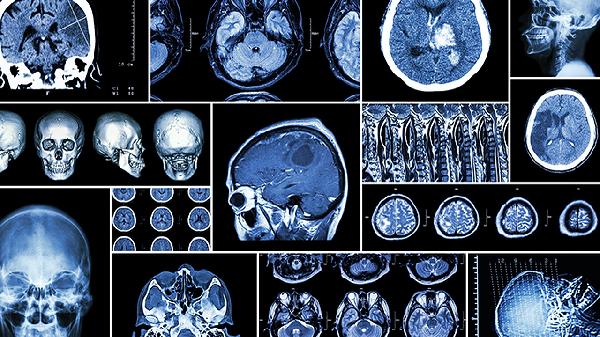

脑溢血属于神经科急症,一旦出现上述症状须立即拨打急救电话。送医前应保持患者安静平卧,避免搬动头部,松开领口保持呼吸通畅。有呕吐时需清理口腔异物防止窒息,禁止喂食任何食物或药物。患者需在具备卒中中心的医院进行头部CT检查确诊,治疗包括控制血压、降低颅内压及必要时手术治疗。康复期需在医生指导下进行肢体功能训练和语言康复,控制高血压等基础疾病,调整低盐低脂饮食,戒烟限酒,定期复查脑血管情况。